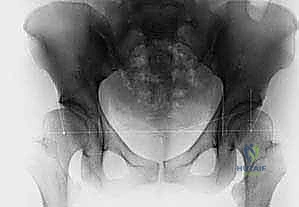

- الأشعة السينية (X-rays): تُستخدم للأطفال الأكبر من 6 أشهر بعد بدء تعظم رأس الفخذ.

6. التصوير الإشعاعي داخل العمليات:

خلال جميع هذه الخطوات، يتم استخدام جهاز الأشعة السينية المحمول (C-arm) للتأكد من أن المفصل في وضعه المثالي والتشريحي بنسبة 100%.

صور إضافية لخطوات الجراحة الدقيقة والمتابعة الإشعاعية

يوثق الأستاذ الدكتور محمد هطيف كل خطوة جراحية لضمان أعلى معايير الجودة والشفافية الطبية.